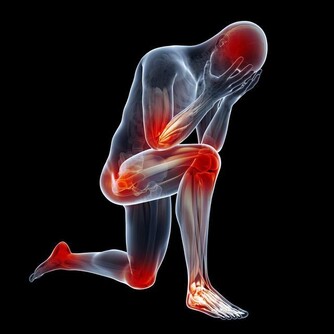

腎病被稱為〝沉默殺手〞,就算腎受傷了,你可能也毫無感覺。

你經常在新聞中看到,某人因食慾減退、貧血或疲勞乏力去就醫,卻發現已經是尿毒癥晚期!

第四名:過度勞累強度較大的工作導致身體疲勞,從而引發腎虛癥狀。

其次用腦過度,巨大的工作壓力和生活壓力導致精神無法放鬆,腦力勞動累,也容易傷腎。

第六名:突然劇烈運動工作忙碌長期不運動,突然劇烈運動可能會造成你的腎過度損傷,嚴重的會導致急性腎衰竭。

第十名:壓力大、心情煩躁現代人的工作、生活壓力都很大,〝我很煩〞也就成了很多人的口頭禪。而這些情緒也會傷腎。